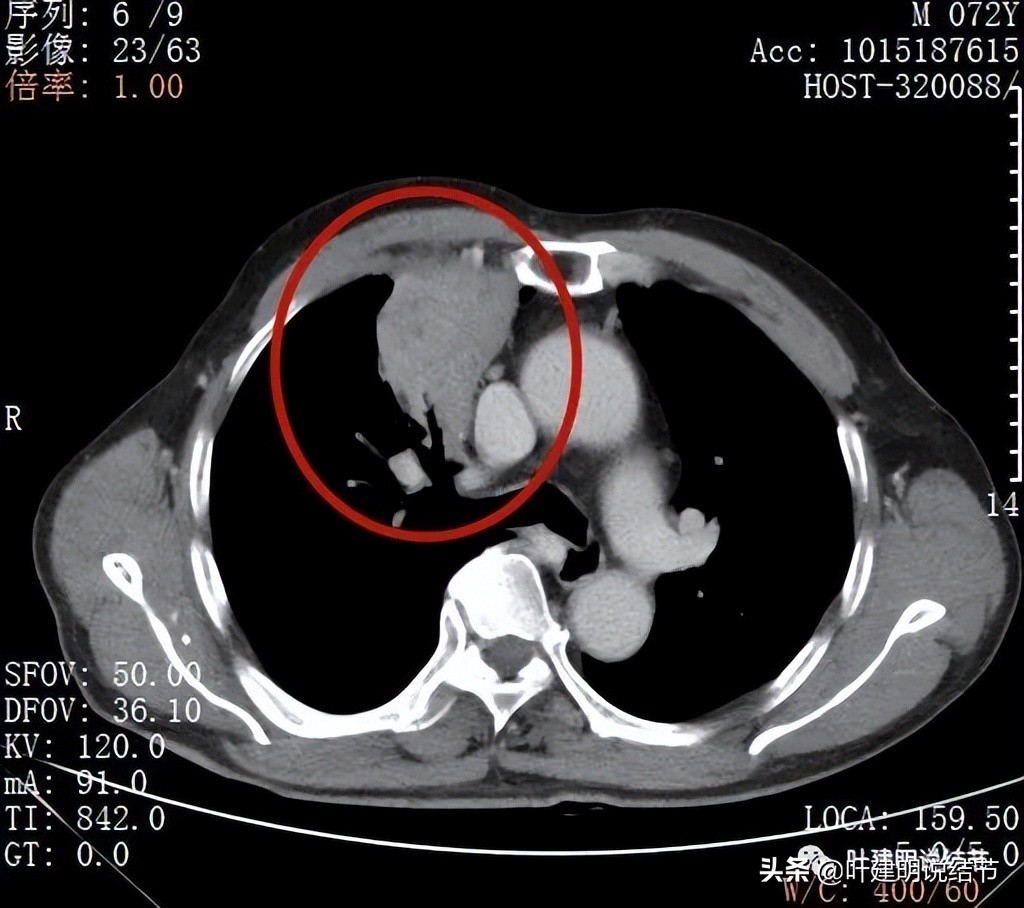

纵隔窗见肿块巨大,内部密度略不均